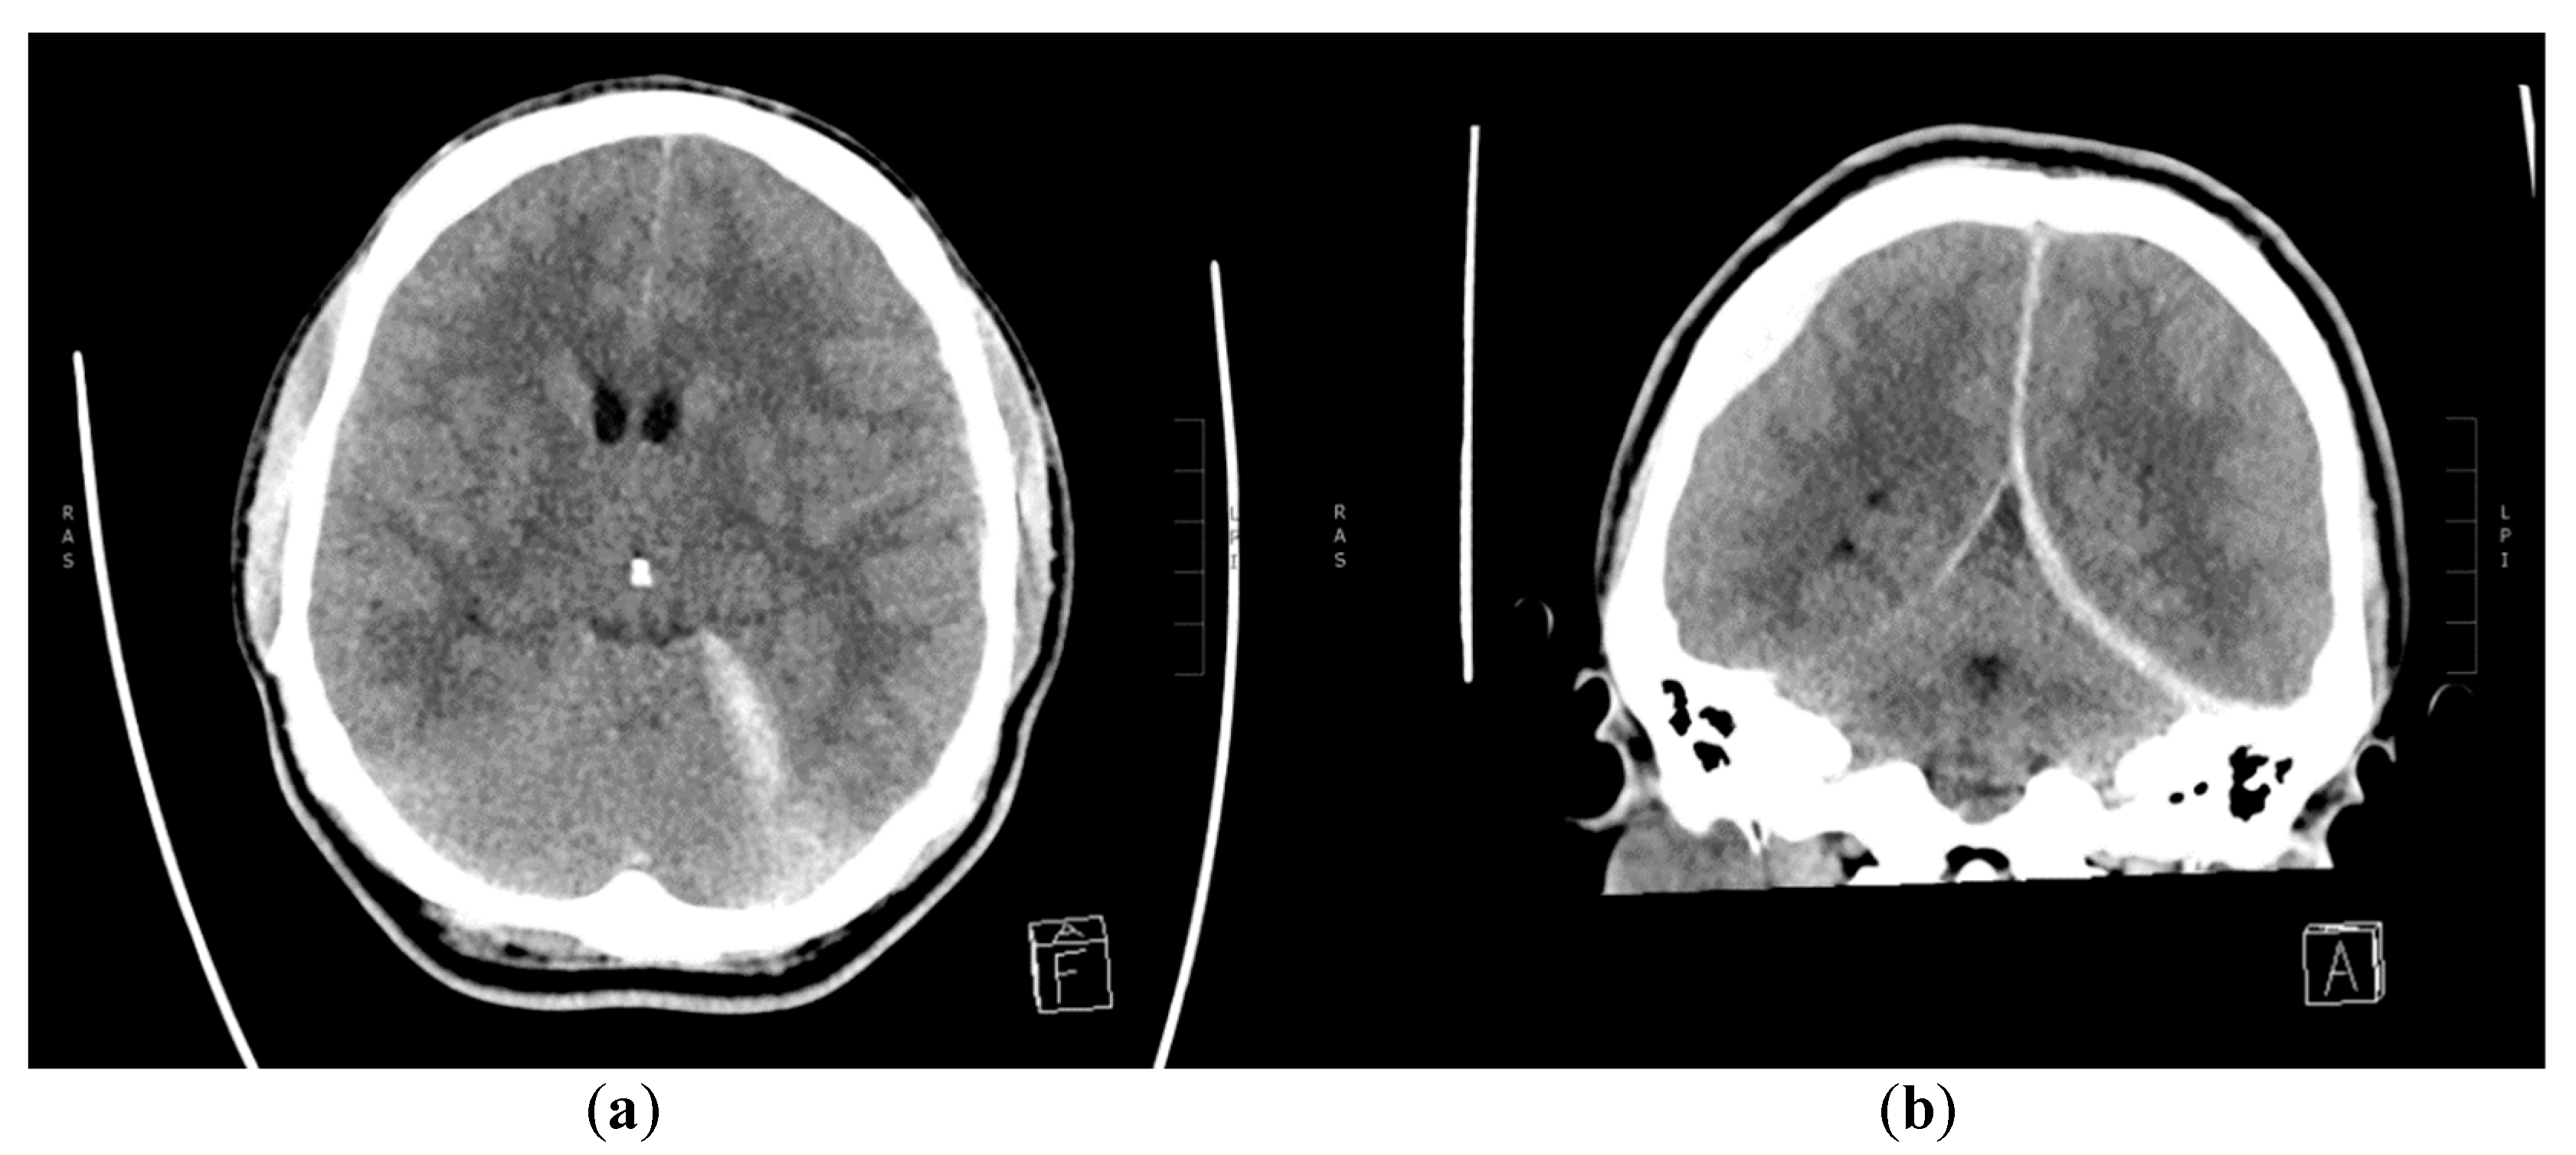

2. Case Report